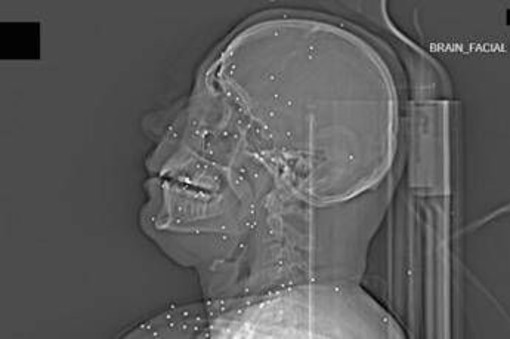

Il volto di Anahita – nome di fantasia, poco più che ventenne – appare come un cielo notturno attraversato da punti luminosi. Piccole sfere metalliche, da 2 a 5 millimetri, disseminate sul viso, nelle orbite oculari, persino nella massa scura del cervello. Sono proiettili “birdshot”, pallini da caccia sparati da un fucile a pompa. A distanza ravvicinata, spiegano gli esperti, non sono affatto “meno letali”: possono frantumare ossa, devastare tessuti molli, perforare facilmente un bulbo oculare. Anahita ha perso almeno un occhio, forse entrambi.

Quell’immagine non è un caso isolato. Fa parte di oltre 75 set di esami diagnostici provenienti da un singolo ospedale di una grande città iraniana, raccolti nel corso di una sola serata, durante la stretta repressiva di gennaio. Una concentrazione temporale che, già di per sé, racconta una dinamica da “mass casualty”, evento con numerose vittime simultanee, tipico degli scenari di guerra o dei grandi disastri.

Le valutazioni, condotte congiuntamente dal Guardian e dalla piattaforma di fact-checking Factnameh, sono state affidate a un panel indipendente di specialisti internazionali: medici d’urgenza, radiologi, esperti di trauma imaging e balistica. Un ex medico iraniano di pronto soccorso, anch’egli consultato, ha confermato la coerenza del software utilizzato per gli esami e l’assenza di segni di manomissione. Gli esperti precisano che, senza cartelle cliniche complete, non è possibile formulare diagnosi definitive sui singoli pazienti. Ma il quadro complessivo, spiegano, è inequivocabile.

“Se spari con armi di quel tipo contro delle persone, stai cercando di ucciderle.” La frase di uno degli specialisti di imaging traumatico riassume la sostanza tecnica dell’inchiesta. Le immagini mostrano proiettili full metal jacket, tipicamente utilizzati nei fucili d’assalto come AK-47 o KL-133, armi in dotazione ai Pasdaran, il Corpo delle guardie rivoluzionarie islamiche (IRGC). Non strumenti di controllo della folla, ma armamenti progettati per la guerra.

Accanto ai colpi di grosso calibro, emerge con forza un altro elemento: l’uso sistematico dei pallini metallici. L’Iran è tra i pochi Paesi in cui le forze di sicurezza impiegano birdshot metallico. A lunga distanza, i pallini si disperdono e colpiscono indiscriminatamente. A distanza ravvicinata, diventano devastanti: decine, talvolta centinaia di micro-proiettili che penetrano simultaneamente nei tessuti.

Le radiografie raccontano questa brutalità in modo quasi didascalico. Il torace di Ali – anche qui, nome di fantasia – contiene oltre 174 pallini metallici concentrati nella cavità destra. Il polmone parzialmente collassato, circondato da sangue e gas. Secondo gli esperti consultati, anche con un intervento chirurgico immediato e massiccio, il rischio di morte rimane altissimo.